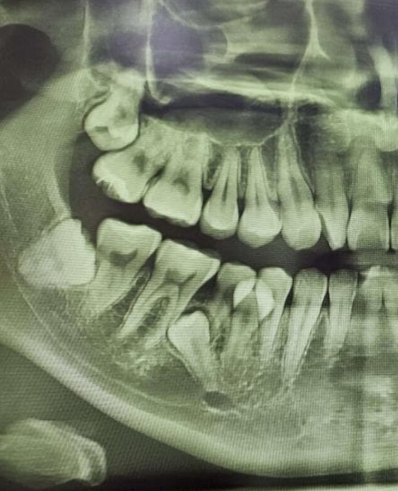

어느 날 갑자기 잇몸 구석이 욱신거리기 시작했다면, 그것은 인류 진화의 흔적이자 치과 의사들의 영원한 숙제인 사랑니가 존재감을 드러낸 신호일 가능성이 큽니다. 사랑니는 예쁘게 나서 제 역할을 하면 좋으련만, 보통은 좁은 잇몸 틈바구니에서 옆 치아를 괴롭히거나 매복되어 염증을 일으키기 일쑤입니다.

하지만 잇몸을 째고 치아를 쪼개서 꺼내야 하는 매복 발치나 복잡 발치로 넘어가면 비용은 3만 원에서 5만 원 선으로 올라갑니다. 만약 대학병원 같은 상급종합병원으로 원정을 떠난다면 기본 진찰료가 비싸지기 때문에 비용이 조금 더 추가될 수 있습니다.